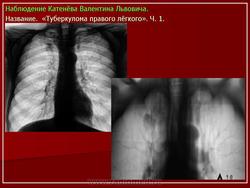

1. Множственные туберкулемы с распадом. В верхней доле правого легкого расположены множественные округлые тени, диаметром 1.5-2 см. средней интенсивности, с просветлением в центре, с четкими контурами.

2. Туберкулема в фазе распада. На томограммах в верхней долях правого и левого легкого определяются округлые тени, с четкими контурами, размерами 6 х 7 см. средней интенсивности, с просветлениями внутри.